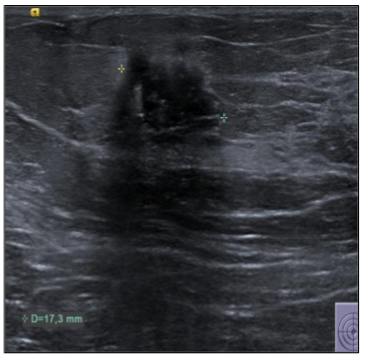

In September 2019, a 69-year-old woman presented to the emergency department of the University Hospital Città della Salute e della Scienza – Turin (Italy), reporting extreme fatigue and dyspnea. She had no comorbidities except for a medical history of papillary thyroid cancer, treated with thyroidectomy and radiotherapy 13 years before. Her complete blood count revealed anemia, thrombocytopenia and leukocytosis (Hb: 7.8 g/dL, PLT: 37 × 109/L, WBC: 45 × 109/L), while her physical examination was normal. The bone marrow smear showed 84% of blasts with myeloid immunophenotype (CD45, CD13, CD33, HLA-DR, lysozyme, CD36, CD64, CD11bc, partial CD14, and CD4 positive), molecular biology showed NPM1 mutation and FLT3-ITD positivity, while karyotype was normal (46, XX, 20/20). Consequently, a diagnosis of FLT3-ITD+ and NPM1 mutated t-AML was made. Induction chemotherapy was started with CPX-351 (liposomal daunorubicin 44 mg/m2 and cytarabine 100 mg/m2), obtaining CR with a 3-log NPM1 reduction (0.177). She was consolidated with CPX-351 (liposomal daunorubicin 29 mg/m2 and cytarabine 65 mg/m2 day 1 and 3), remaining in CR with persistent low level of measurable residual disease (MRD), NPM1 0.34. Meanwhile, we found a suitable HLA matched donor, but the patient refused the transplant procedure. Thus, we decided to start off-label azacitidine as maintenance therapy (50 mg/m2 subcutaneous daily for 5 days, every 28 days). Maintenance therapy was globally well tolerated, and the patient experienced only positivity for COVID-19 without need of hospitalization or additional care. She remained in CR with persistent MRD in BM (NPM1 0.044 after 12 cycles). During the fifteen course (May 2021), we found a palpable right mammary nodule on physical examination, confirmed on ultrasound, with a diameter of 18 x 11 mm. We stopped azacitidine and we promptly biopsied the nodule with a diagnosis of breast infiltration by AML blasts carrying the NPM1 mutation. CT scan and PET of chest, neck and abdomen were negative, and BM evaluation showed 1% blasts, with NPM1 0.044. The FLT3-ITD mutation resulted positive on breast cells while negative on medullary blasts. Thus, concluding for extramedullary relapse of AML FLT3-ITD mutated, we decided to start gilteritinib as single agent, at a dose of 120 mg daily. After 30 days, mammary ultrasound showed a reduction in diameter of the nodule, and in 4 months, the lesion has completely disappeared. The PET scan performed after 5 months of treatment was persistently negative and confirmed the absence of other uptakes. BM re-evaluation showed no blasts, with NPM1 0.006. Today, after 44 months of treatment, our patient is still in CR without signs of clinical and radiologic relapse. We continue monitoring her MRD status every two months on peripheral blood, as shown in table 1. Globally, therapy has been always well tolerated. In January 2024, we had to stop gilteritinib for 28 days due to pyelonephritis and sepsis treated with broad spectrum antibiotics. During this time, she remained in complete remission without any sign of relapse. After some months, in September, our patient has undergone exeresis of basal cell carcinoma, without complications and without need of stopping gilteritinib.

Myeloid sarcoma (MS), also referred to as extramedullary myeloid infiltration, was first described in 1811 by Burns. Initially, the tumor was called “chloroma” because of its greenish hue, which was later linked to the presence of the MPO (myeloperoxidase) enzyme by King in 1853. The tumor was identified as a mass composed of myeloid blasts, causing disruption in the normal tissue structure. The connection between MS and myeloid leukemia was first established in 1893 by Dock. Histologically, MS consists of immature granulocyte precursors, such as myeloblasts, promyelocytes, myelocytes, and granulocytes. Core biopsy is preferred over fine needle aspiration for the histologic and immunophenotypic evaluation, FISH, PCR and NGS allows a better understanding of the patient’s prognosis and identification of potential treatment targets. It is observed in 3-8% of adult patients with acute myeloid leukemia. It can occur in the context of intramedullary AML (synchronous extramedullary AML), or in an isolated form with an essentially normal bone marrow (isolated extramedullary AML; also called “nonleukemic” or “aleukemic”), which is usually followed by the development of metachronous intramedullary AML. Its frequency is higher in the post-allo-HSCT relapse setting with about 15% of all post allo-HSCT AML relapses being isolated EMI. While the exact cause of MS development remains unclear, it is thought to involve the migration of leukemia blasts to extramedullary sites, facilitated by specific adhesion molecules found on the blast cell surfaces. Age might influence the presence of MS; most studies have reported a median age at diagnosis ranging from 46 to 59 years, with approximately 52–59% of affected patients being male. Certain genetic features, including trisomy 8, monocytoid differentiation of blasts, MLL rearrangements, as well as CD56 positivity and the absence of CD117 (c-kit), are associated with an increased risk of developing MS in AML. These factors enhance the ability of leukemic cells to migrate to areas beyond the bone marrow. Recent reports have highlighted the frequent occurrence of FLT3 mutations in patients with EMI. FLT3-ITD mutations were the first molecular abnormalities to be identified in MS cells with initial studies detecting the mutation in up to about 30%, which is similar to the frequency noted for typical AML. NPM1 mutations are detected in up to 50% of cases, again comparable to conventional AML. MS in the breast is extremely rare, making up only about 3% of all MS cases, according to a Mayo Clinic study. Due to its infrequency, it is often mistaken for other breast malignancies, such as lobular carcinoma, non-Hodgkin’s lymphoma, or small round blue cell tumors. A recent review by Sharma et al. examined 67 previously reported cases, 66 of which were women and only one was a man. In most instances, breast MS presents as a rapidly enlarging mass, which may affect one or both breasts. Nipple retraction is generally not observed. Right-sided breast involvement is more common than left-sided. In terms of imaging, MS in the breast typically appears as a large, irregular, non-calcified mass with poorly defined, “feathery” margins, a characteristic finding consistent with the mammograms of the patients in the study. FDG-PET/CT at diagnosis, after treatment completion and at the time of suspected relapse is an important tool that allows for timely adjustments to the management strategy.